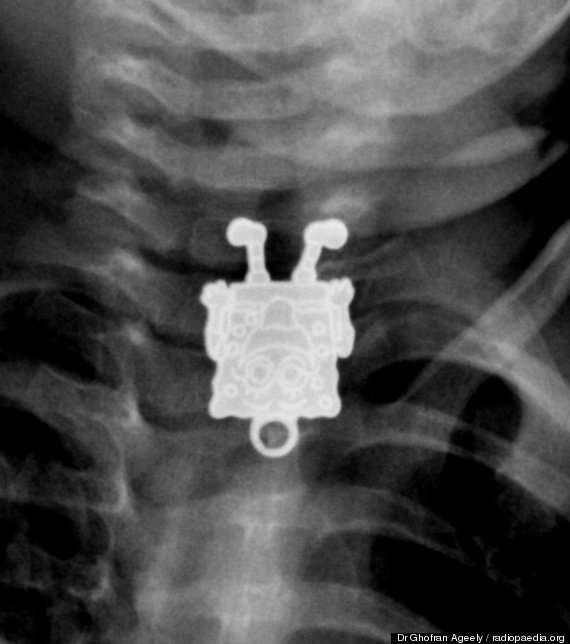

استخرج أطباء لعبة “سبونج بوب” الكارتونية الشهيرة من مرئ رضيع بعد أن استقرت فيه وكادت تودي بحياته لولا التدخل الجراحي.

ونجح الأطباء بمستشفى الملك عبدالعزيز في السعودية في استخراج سبونج بوب من مريء الرضيع البالغ من العمر 16 شهراً.

وأحضر أب طفلهُ الرضيع إلى المستشفى، مخبراً عن أنه ابتلع قطعة غير معروفة، وبإجراء الأشعة فوجئ الأطباء بوجود بوجه سبونج بوب يبتسم لهم في الاشعة السينية ما أصابهم للوهلة الأولي بالدهشة.

وفوراً أجرى الأطباء جراحة للطفل لاستخراج القطعة قبل أن تسبب تهديداً لحياة الرضيع.

و نشرت إحدى أخصائيات الأشعة بمستشفى الملك عبدالعزيز صوراً للأشعة السينية ويظهر فيها سبونج بوب، مشيرة إلى أنها للوهلة الأولى بعد اطلاعها على الصورة الجانبية ظنت أن الطفل ابتلع قلماً، إلا أنها تفاجأت بعد ذلك من الصور الأمامية بأنها قلادة على شكل “سبونج بوب”.